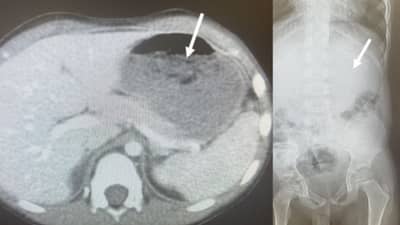

अमेरिकेतील ओहीओ येथील एका चार वर्षीय बालकाने एकाच वेळी चाळीस च्युईंग गम गिळल्याचा धक्कादायक प्रकार घडला. त्यानंतर या मुला अतिसार आणि स्नायूंना पेटके येण्याचा त्रास सुरु झाला. या मुलाला क्लीव्हलॅंड क्लिनिक येथे नेण्यात आले. क्लीव्हलँड क्लिनिकमधील डॉ. चिझिट यांच्या नेतृत्वाखाली डॉक्टरांच्या पथकाने या मुलाचा सीटी स्कॅन काढला. तेव्हा त्याच्या पोटात च्यईंग गमचा थर असल्याचे दिसून आले. त्यानंतर या मुलाच्या घशातून च्युईंग गमचा गठ्ठा खेचून बाहेर काढावा लागला. या मुलाचे नाव गुप्त ठेवण्यात आले आहे. घशातून च्युईंगम काढल्याने त्याचा घसा काही काळ दुखू लागला होता. परंतू त्याव्यतिरिक्त त्याच्यावर या प्रक्रियेचा दीर्घकालीन परिणाम झाला नाही.

सीटी स्कॅनमध्ये त्याच्या पोटात बाह्य पदार्थ अडकल्याचे दिसून त्याने पोटाचा 25 टक्के भाग व्यापल्याचे दिसले. डॉक्टरांनी या मुलावर उपचार कसे करावेत यावर चर्चा केली. अखेर अन्ननलिकेतून हे च्युईंग गम अनेक प्रयत्न करून काढण्याचा निर्णय घेण्यात आला. डॉक्टरांनी पोकळ धातूची नळी घशातून टाकत च्युईंग गमचे तुकडे बाहेर काढले. अनेक प्रयत्न करीत नळीद्वारे हे च्युईंग गम बाहेर काढले गेले, संपूर्ण ऑपरेशन दरम्यान मुलगा शांत राहील्याने सोपे गेले.